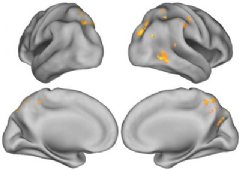

The human brain is capable of a neural workaround that compensates for the buildup of beta-amyloid, a destructive protein associated with Alzheimer’s disease, according to a new study led by UC Berkeley researchers.

“Generally, the groups performed equally well in the tasks, but it turned out that for people with beta-amyloid deposits in the brain, the more detailed and complex their memory, the more brain activity there was,” said Jagust. “It seems that their brain has found a way to compensate for the presence of the proteins associated with Alzheimer’s.”